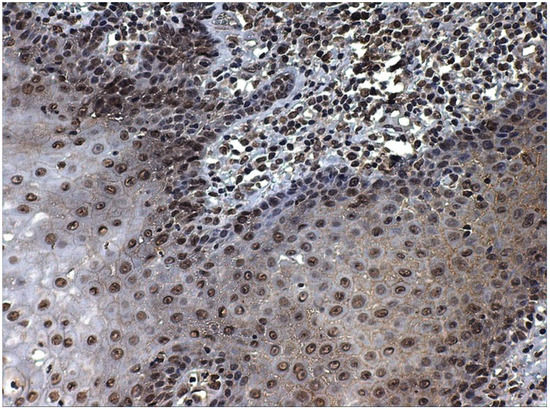

- Moles, M.A.G.; Esteban, F.; Ruiz-Avila, I.; Montoya, J.A.G.; Brener, S.; Bascones-Martínez, A.; Muñoz, M. A role for the substance P/NK-1 receptor complex in cell proliferation and apoptosis in oral lichen planus. Oral Dis. 2009, 15, 162–169. [Google Scholar] [CrossRef] [PubMed]

- González-Moles, M.A.; Brener, S.; Ruiz-Avila, I.; Gil-Montoya, J.A.; Tostes, D.; Bravo, M.; Esteban, F. Substance P and NK-1R expression in oral precancerous epithelium. Oncol. Rep. 2009, 22, 1325–1331. [Google Scholar] [CrossRef][Green Version]

- Brener, S.; González-Moles, M.A.; Tostes, D.; Esteban, F.; Gil-Montoya, J.A.; Ruiz-Avila, I.; Bravo, M.; Muñoz, M. A role for the substance P/NK-1 receptor complex in cell proliferation in oral squamous cell carcinoma. Anticancer Res. 2009, 29, 2323–2329. [Google Scholar]